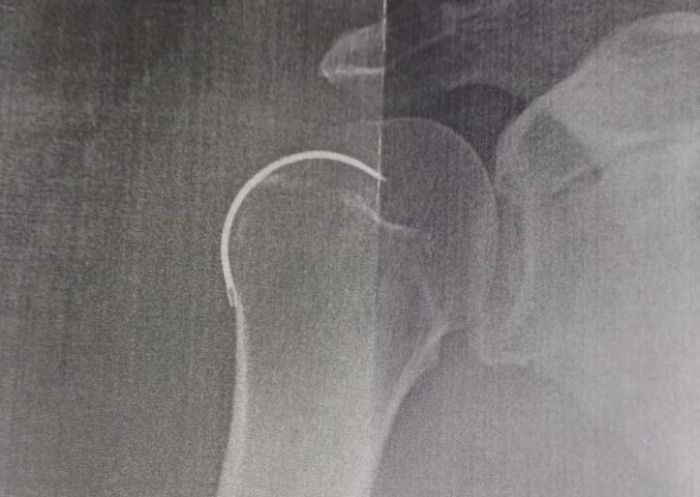

Médico esquece agulha em paciente após cirurgia em Armazém; homem ficou 5 meses com objeto no ombro

Após cinco meses de dores constantes, raio-X revelou objeto deixado no corpo de Josoel Serafim, de 62 anos

Josoel Geraldo Serafim, de 62 anos, é morador de Capivari de Baixo e passou por uma cirurgia no ombro direito no dia 6 de outubro de 2024, no Hospital Santo Antônio, em Armazém. No entanto, o procedimento teve uma grave falha: o médico esqueceu uma agulha de sutura dentro do ombro do paciente.Por cinco meses, Josoel enfrentou dores constantes e procurou atendimento médico diversas vezes. Em todas as consultas, foi informado de que os sintomas eram normais no pós-operatório. Somente após um novo raio-X, os médicos descobriram a presença do objeto cirúrgico esquecido.